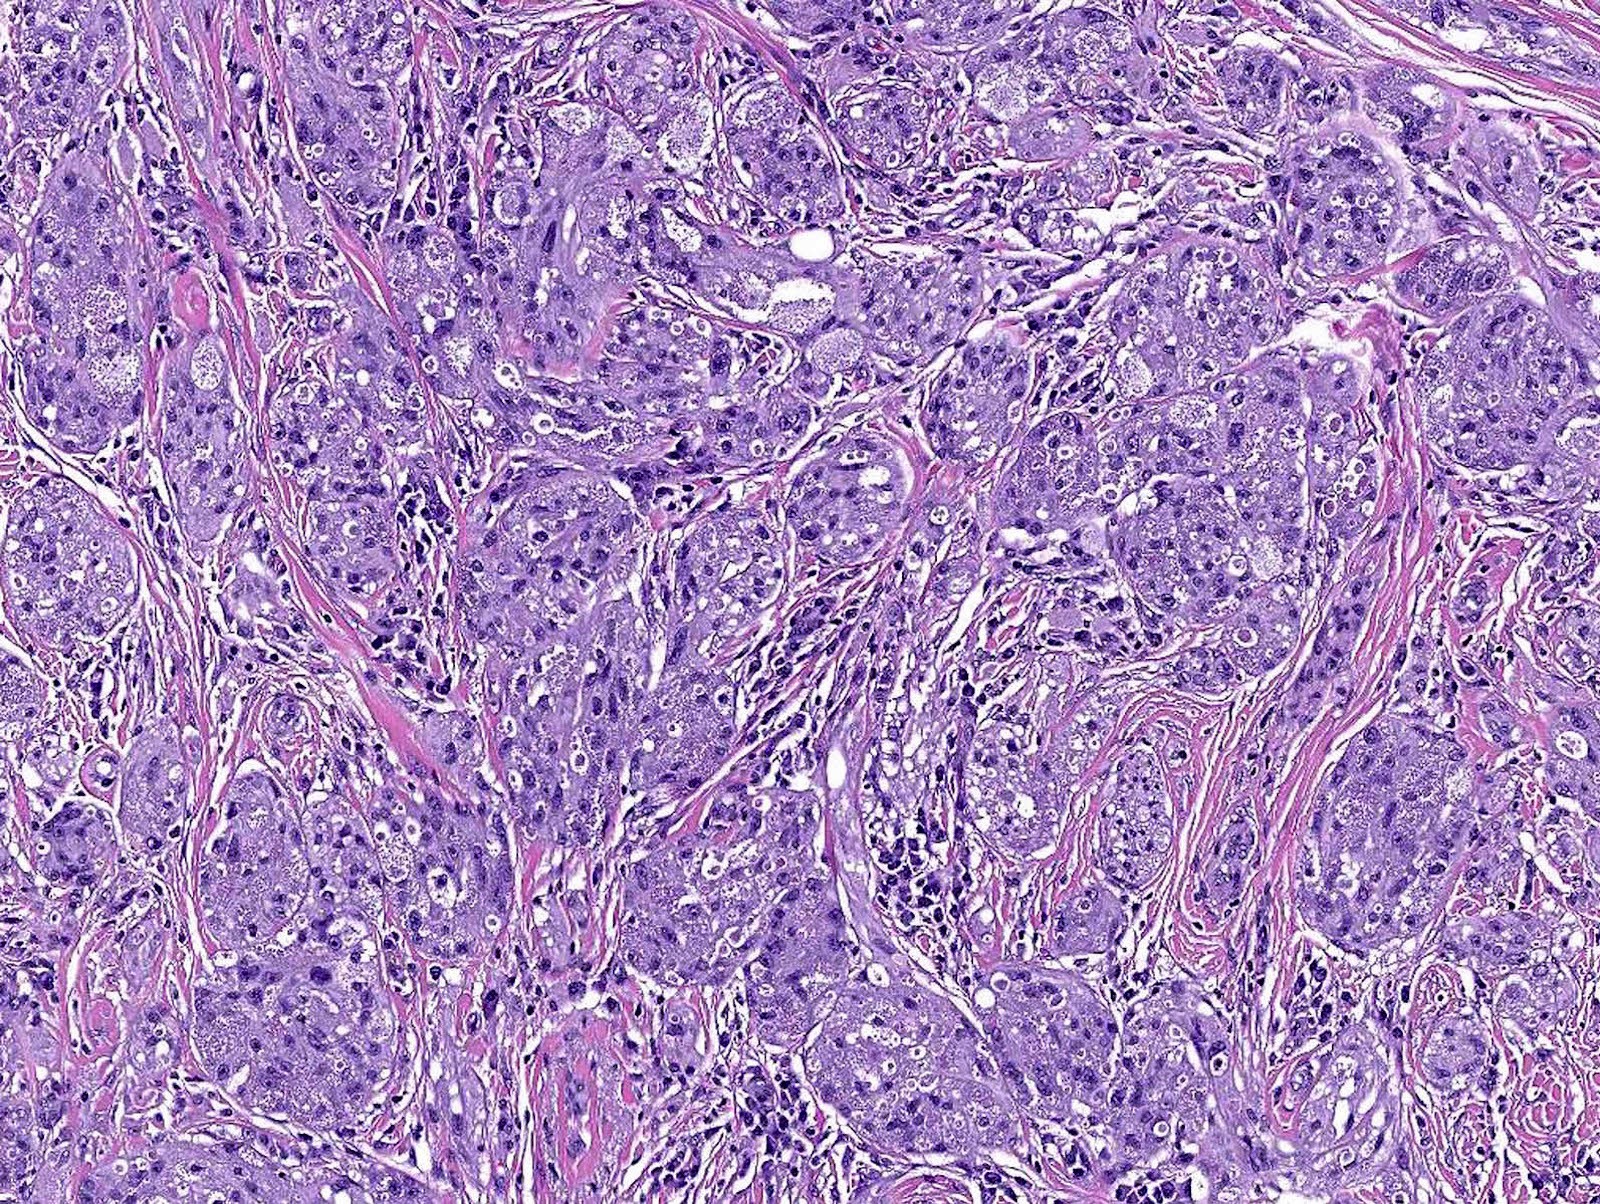

Microscopic (histologic) description

- Infiltrative or circumscribed architecture

- Large polygonal cells with abundant eosinophilic granular cytoplasm and small, central nuclei

- Lysosomal macroinclusions (pustulo-ovoid bodies of Milian) are usually present (J Cutan Pathol 2007;34:405)

- Can exhibit accentuation around arrector pili muscles or peripheral nerves (J Clin Pathol 2014;67:19)

Microscopic (histologic) images

Contributed by Jarish Cohen, M.D., Ph.D.